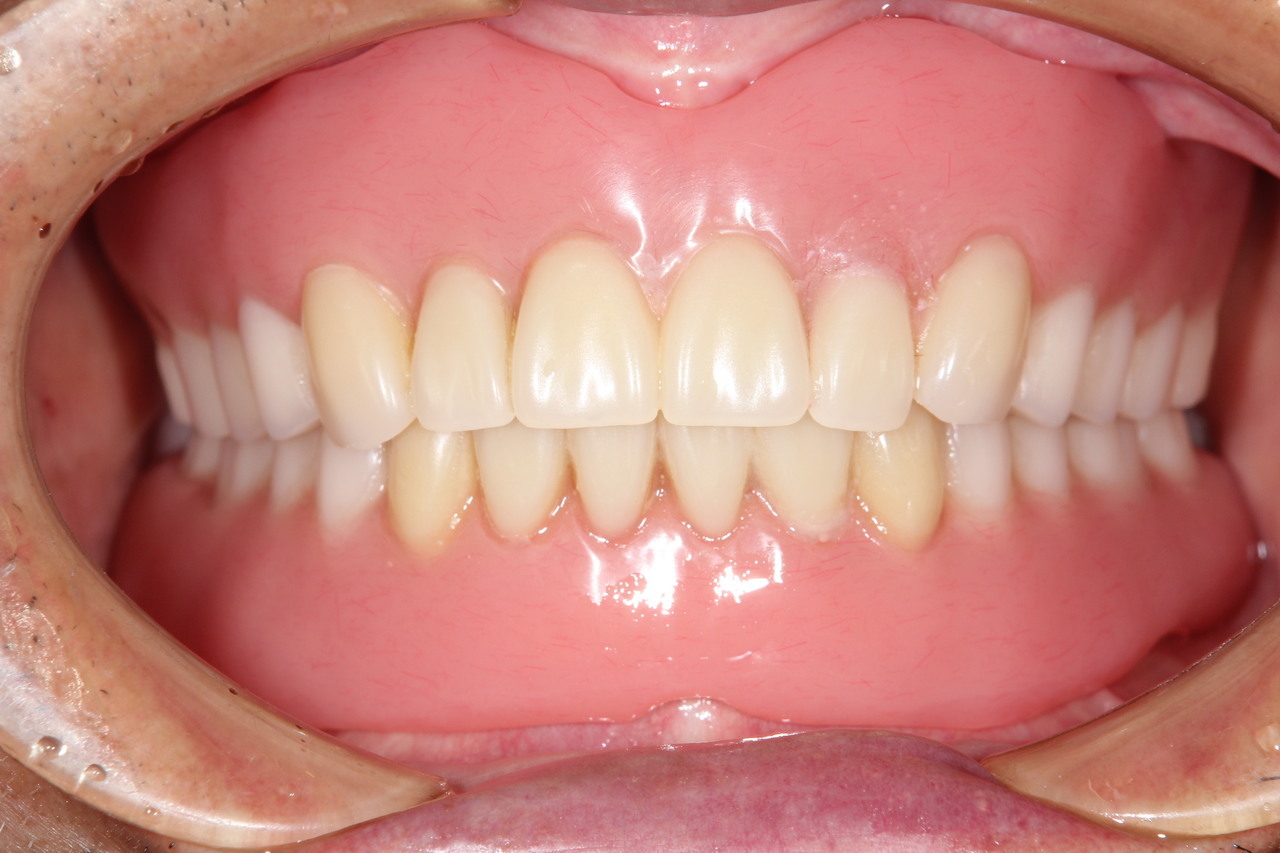

最終的な被せ物装着

インプラントがしっかり骨に定着したら、型取りをして、最終的な被せ物を製作し、装着します。

6本のインプラントを埋入し、12本の歯を並べています。第二大臼歯を作らない場合の理想的な治療法になります。